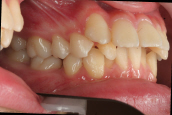

18歳の女の子です。家の近くの矯正専門医で治療が難しいと言われ、大学病院に紹介された患者さんです。

大学病院では顎を切る手術の矯正になると言われ、同時に小さな奥歯を4本抜歯する必要があると言われたそうです。なぜ このような乱ぐい歯になったのでしょう?その考察がなく、見た目の乱ぐいだけを考えたのでは、本当の意味での治療にはならないと思います。なぜ このような成長方向になったのでしょうか。

初診時です